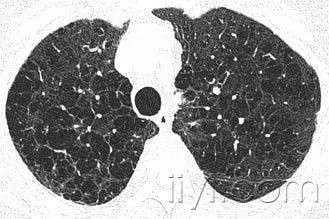

附图为小叶中心性肺气肿 医学百科网 | YxBaike.Com

CT:正常次级肺小叶中心的点状或者线状的密度增高影,胸膜下25px范围内最明显,代表小叶内的动脉,直径约1mm。小叶中心性异常包括(1)结节(2)树芽征,提示小气道病变(3)由于临近间质的增厚或者浸润导致小叶中心结果更加清晰(4)小叶中心性肺气肿导致的异常低密度。 医学百科网 | YxBaike.Com